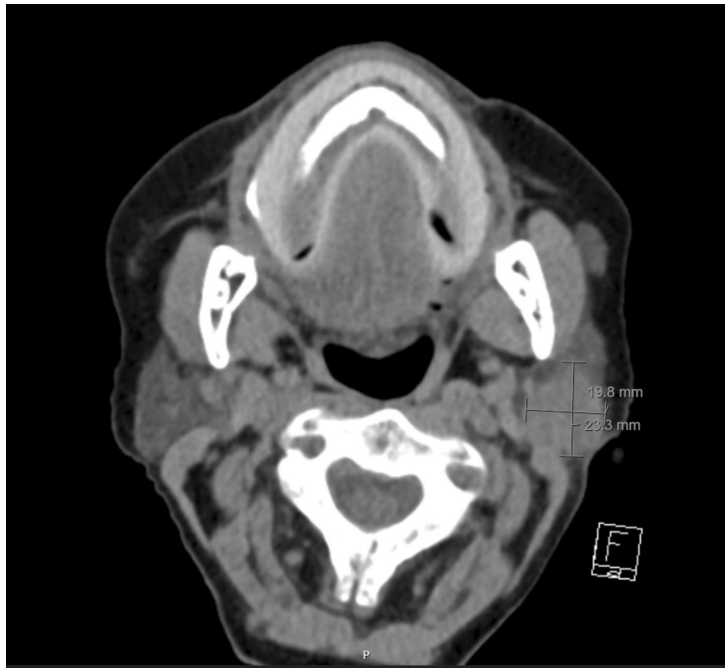

研究结果部分,"Case Presentation"详细描述了该患者的诊疗历程:初始诊断为多发性转移的HER2阳性乳腺癌(ER 3+,PR 1+,HER2 3+),经曲妥珠单抗+帕妥珠单抗联合化疗获得长达7年9个月的疾病控制。腮腺转移表现为突发性下颌角无痛性肿块,CT显示浅深叶交界处21 mm分叶状占位。